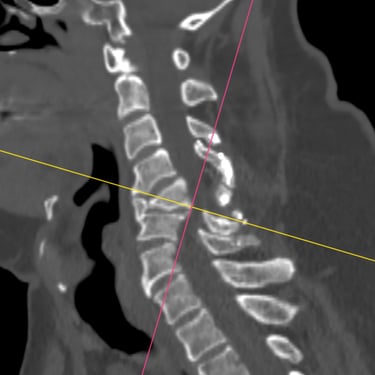

🧠Compresión medular cervical y dorsal: tratamiento mediante artrodesis y descompresión nerviosa.

La compresión medular cervical y dorsal es una patología grave que puede ocasionar déficit neurológico progresivo. La descompresión quirúrgica asociada a artrodesis vertebral permite liberar la médula espinal y estabilizar la columna, mejorando la función neurológica y evitando el deterioro clínico en pacientes adecuadamente seleccionados.